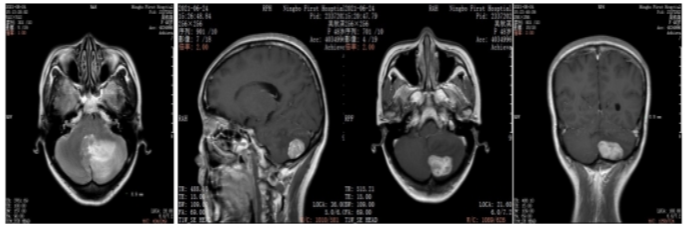

2019年10月乳腺彩超(术前):左乳实性占位(BI-RADS 4c级)。左腋下淋巴结肿大,考虑转移。

图1.乳腺彩超

本例患者术前评估左乳实性占位(BI-RADS 4c级)。左腋下淋巴结肿大,考虑转移。术后病理:ER(-),PR(-),HER2(3+),Ki67(30%)。由于患者的原因,未能做新辅助治疗,缺失了新辅助治疗后的再一次疗效评估,以及对辅助治疗的进一步决策。术后辅助治疗EC-THP(表柔比星+环磷酰胺,序贯多西他赛+赫赛汀+帕捷特),之后辅助曲妥珠单抗(赫赛汀)+帕妥珠单抗(帕捷特)靶向治疗完成1年治疗。在辅助靶向治疗后4月发现单发脑转移病灶。之后行左侧小脑半球肿瘤切除+颅底重建术。脑转移瘤瘤床区放疗。全身系统治疗:汉曲优+吡咯替尼+卡培他滨作为二线治疗,随访中已有15月的PFS,目前仍是CR状态。